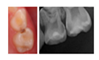

- Case 4: clinical and periapical X-ray showing a proximal ICDAS 5 lesion and an occlusal ICDAS 4 lesion on a second primary molar with a dentine bridge between the lesion and the pulp in a preschool child;